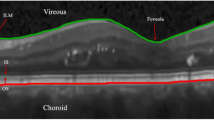

Automatic retinal layer segmentation in optical coherence tomography (OCT) images is crucial for the diagnosis of ocular diseases. Currently, automatic retinal layer segmentation works well with normal OCT images. However, pigment epithelial detachment (PED) dramatically alters the retinal structure, causing blurred boundaries and partial disappearance of the Bruch’s Membrane (BM), thus posing challenges to the segmentation. To tackle these problems, we propose a novel dual-path U-shaped network for simultaneous layer segmentation and boundary regression. This network first designs a feature interaction fusion (FIF) module to strengthen the boundary shape constraints in the layer path. To address the challenge posed by partial BM disappearance and boundary-blurring, we propose a layer boundary repair (LBR) module. This module aims to use contrastive loss to enhance the confidence of blurred boundary regions and refine the segmentation of layer boundaries through the re-prediction head. In addition, we introduce a novel bilateral threshold distance map (BTDM) designed for the boundary path. The BTDM serves to emphasize information within boundary regions. This map, combined with the updated probability map, culminates in topology-guaranteed segmentation results achieved through a topology correction (TC) module. We investigated the proposed network on two severely deformed datasets (i.e., OCTA-500 and Aier-PED) and one slightly deformed dataset (i.e., DUKE). The proposed method achieves an average Dice score of 94.26% on the OCTA-500 dataset, which was 1.5% higher than BAU-Net and outperformed other methods. In the DUKE and Aier-PED datasets, the proposed method achieved average Dice scores of 91.65% and 95.75%, respectively.